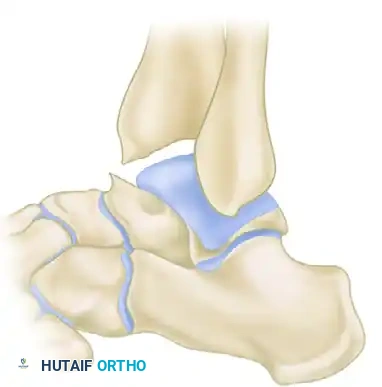

In 1957, O’Donoghue formally directed the orthopedic community's attention to a previously underreported cause of chronic ankle disability: the formation of osteochondral ridges, or exostoses. These bony proliferations typically develop just proximal to the anterior lip of the distal articular surface of the tibia and on the corresponding opposing area of the dorsal surface of the talar neck.

Predominantly observed in athletic populations—particularly footballers, dancers, and runners—these ridges are primarily driven by repetitive biomechanical stress. According to O’Donoghue, the primary etiology is direct mechanical injury sustained during forceful, extreme dorsiflexion of the foot, wherein the neck of the talus is violently thrust against the anterior tibial plafond. Repeated minor microtraumas precipitate a hypertrophic bone response, causing these ridges to enlarge over time. As the exostoses grow, the threshold for collision between the talus and tibia decreases, creating a self-perpetuating cycle of impingement, cartilage abrasion, and further osteophyte formation. These ridges may manifest in isolation on the tibia or the talus, but frequently develop concomitantly on both articular surfaces.

Anterior impingement syndrome is classically an overuse injury of the dorsiflexors, compounded by repetitive microtrauma. The mechanical abutment of the anterior tibial margin against the talar neck leads to the formation of "kissing lesions" or osteophytes.

Grade III (Severe Exostosis): A secondary spur is noted on the dorsum of the talus, often accompanied by fragmentation of the osteophytes (kissing lesions).